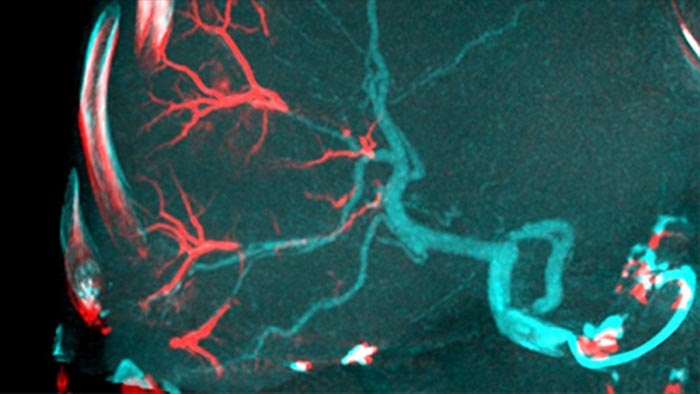

Automatic Feeder Detection solution can significantly improve feeding artery detection. EmboGuide supports you in maximising the efficacy of your TACE procedures as it potentially enhances your sensitivity, reduces false positives and maximises inter-reader agreement1. EmboGuide also provides efficient, workflow-based live 3D guidance with automatic feeder detection1.

Adoption of chemo/radioembolisation techniques such as TACE and SIRT drives the need for standardisation and efficiency. Case after case, you must reliably and consistently locate the tumor(s), identify all feeder vessels, and plan/execute the appropriate interventional approach. Our Automatic Feeder Detection solution can significantly improve feeding artery detection compared to using Cone Beam CT alone. EmboGuide supports you in maximising the efficacy of your TACE procedures as it potentially enhances your sensitivity, reduces false positives and maximises inter-reader agreement.1

The ability to detect and differentiate hepatic nodules and identify tiny feeder vessels is critical to determining proper therapy. Navigating to the region of interest by reaching all feeders, while remaining selective to the lesion, increases the opportunity for success. Confirmation of treatment endpoint and treatment success while the patient is still on the table boosts clinical outcome confidence.